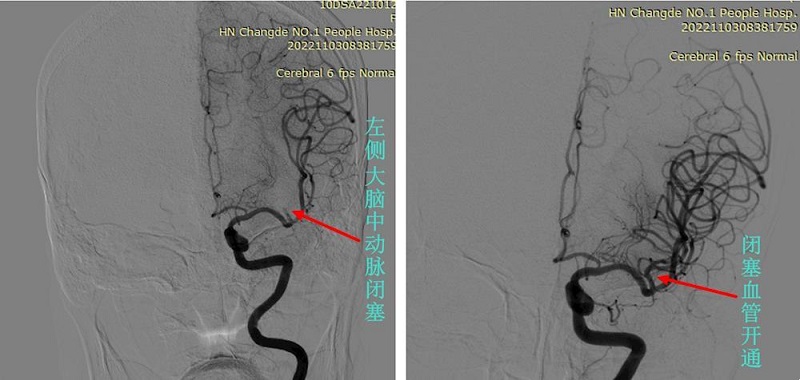

(图左:11月3日,术中脑血管造影显示,静脉溶栓治疗后,张奶奶的左侧大脑中动脉仍然闭塞。图右:左侧大脑中动脉取栓术后,闭塞血管开通)